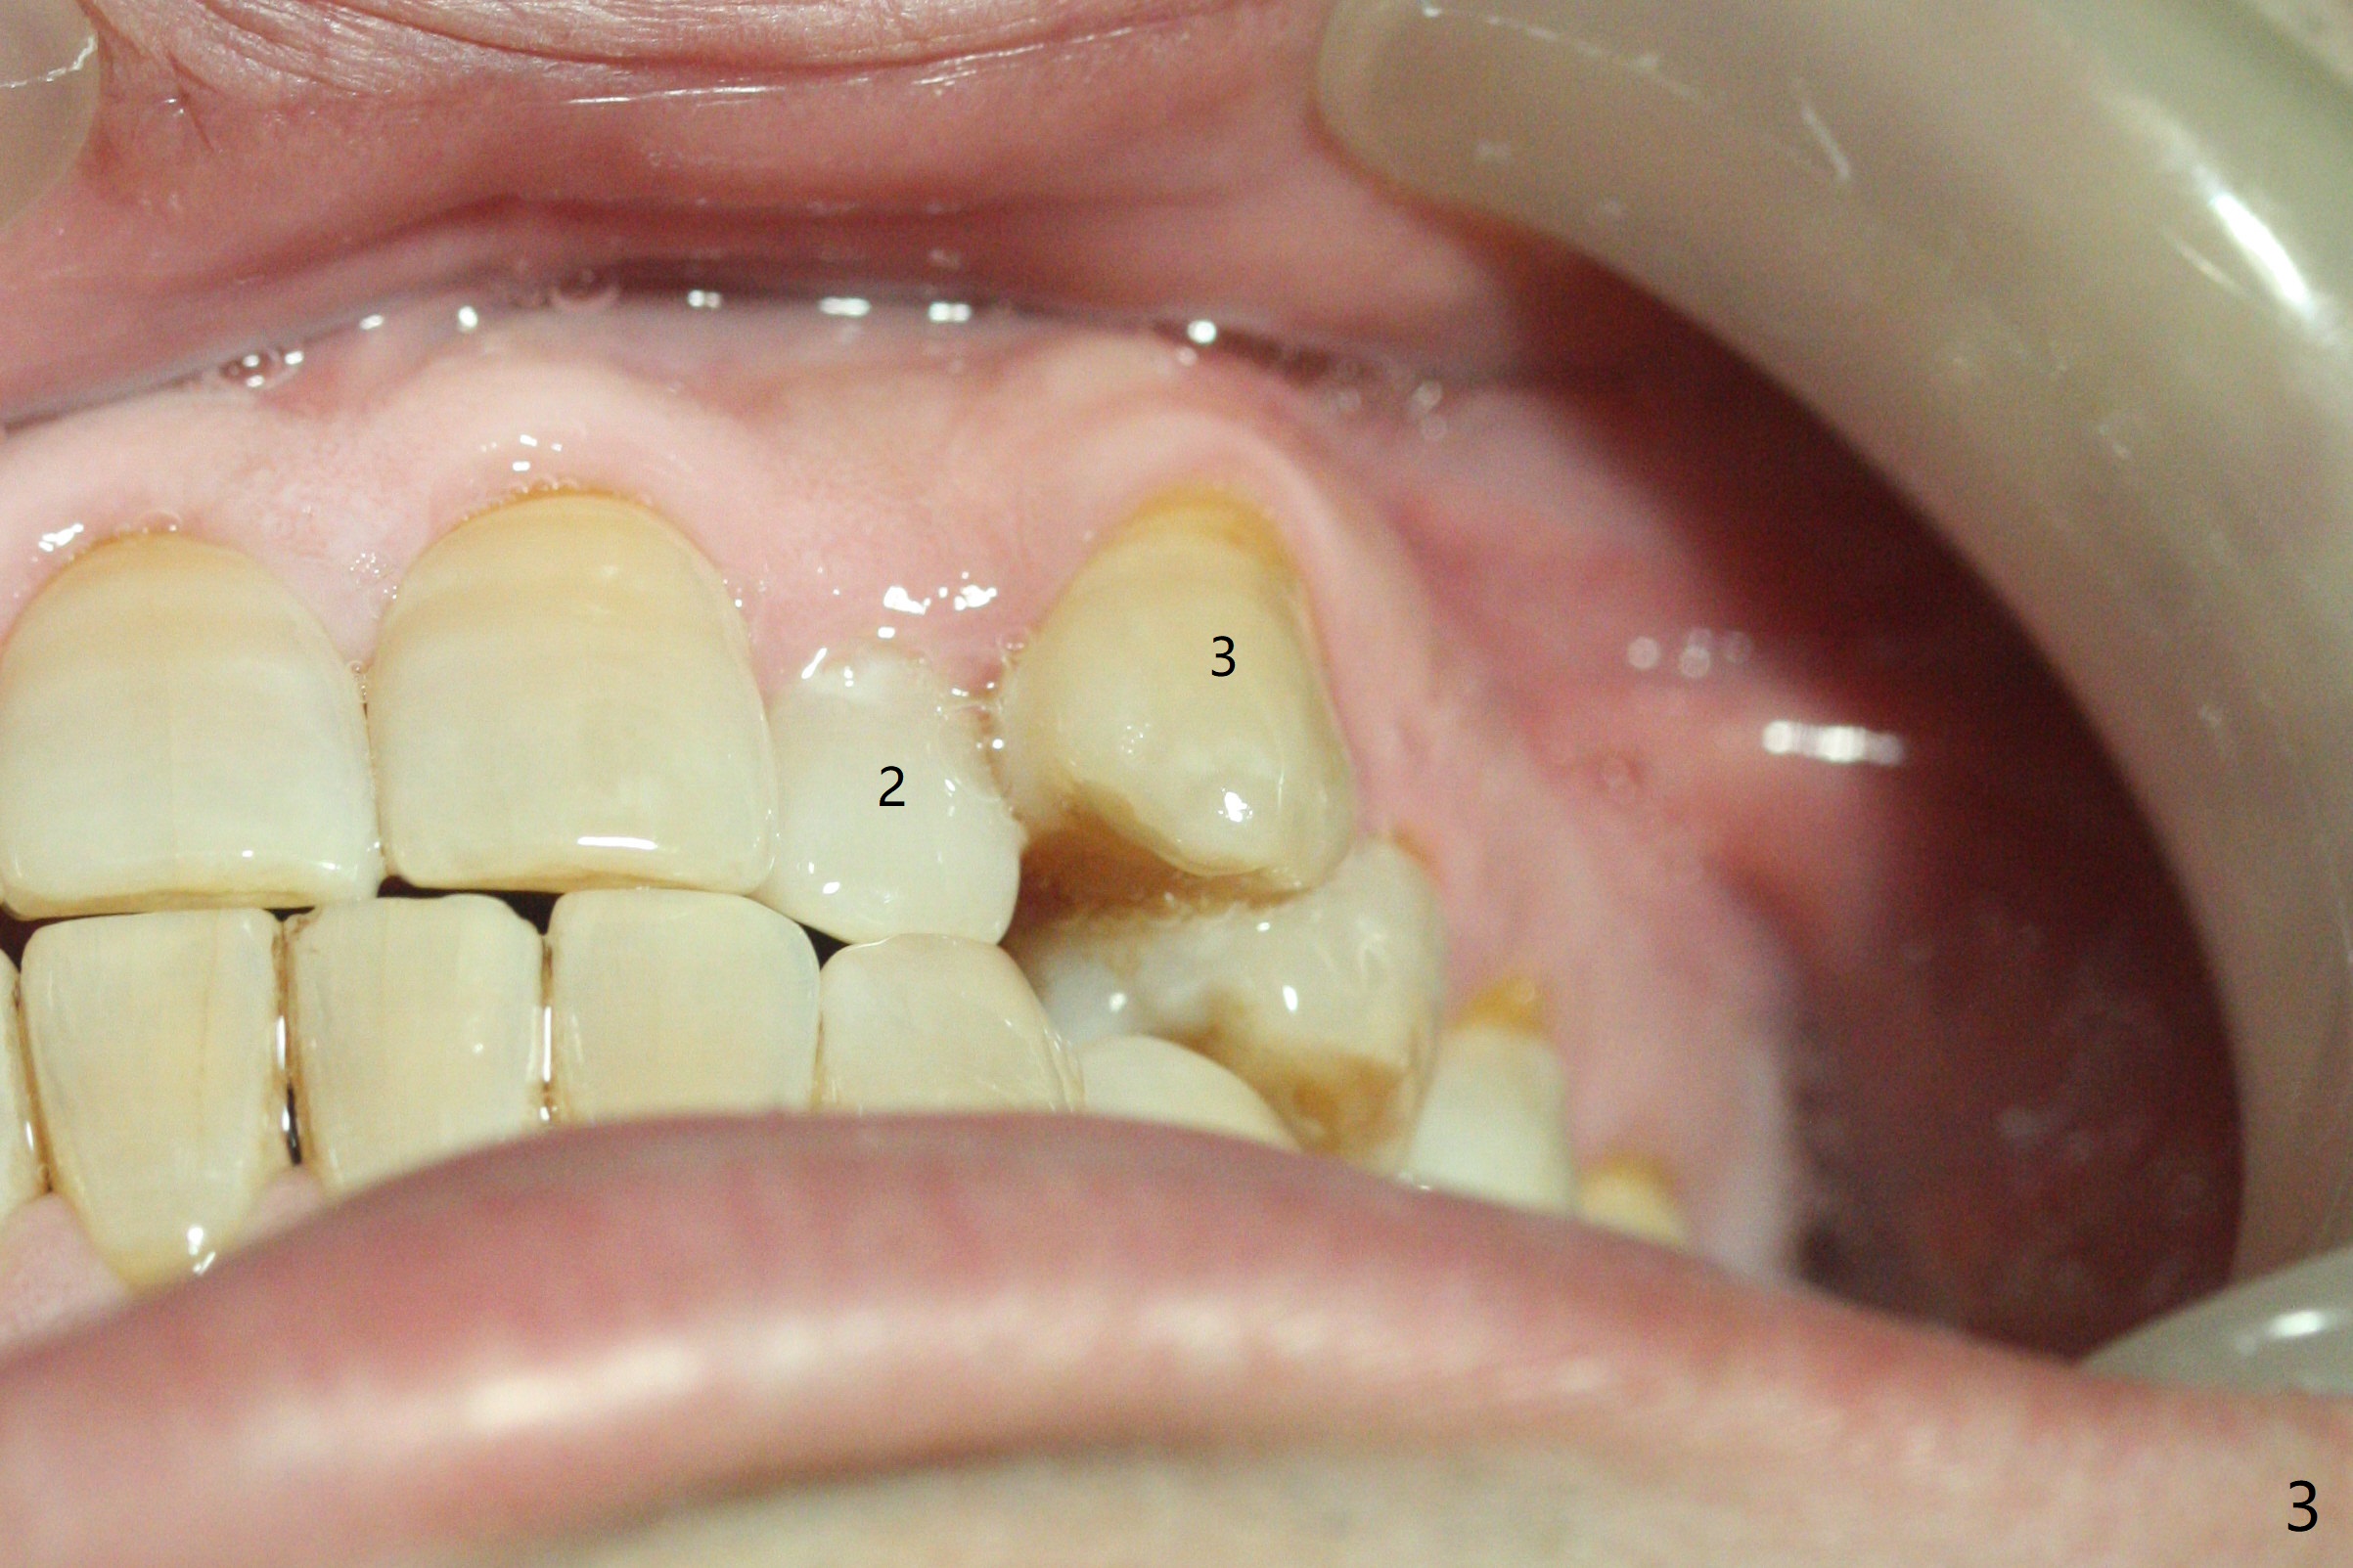

A 40-year-old man requests orthodontics after #17 and 32 extraction. UL5 is missing (Fig.1), while the upper midline deviates to the left (Fig.2 arrow) with crowding between UL2 and 3 (Fig.3). The main goal is to retract UL5 distal and move the upper midline to the right to alleviate UL anterior crowding. Implant will be not needed. To monitor potential root resorption associated with tooth movement, preop PAs are taken (Fig.4-7). The space for an implant at UR5 is narrow. UR4 needs to be distalized using UR7 or a miniimplant distal to UR7 as an anchor (Fig.8). UR4 and 3 will be repositioned to establish Class I occlusion (Fig.9). The space gained by UR4 distalization may be enough to correct the upper midline deviation and UL3 malposition (Fig.10). Brackets will be placed in the lower arch in spite of the normal alignment (Fig.11). UL2 and 3 brackets are unable to be engaged to 14 niti wire (Fig.12). Next visit try to engage UL2 bracket. If not, save the old wire for possible future reuse. Closed spring is placed with 18 ss wire <3 months post banding (coronavirus). Three weeks post closed spring between UR4-7, UR3,4 are being distalized (Fig.13). Distalization of UR4 is not much in 5.5 months (Fig.14,15). It seems necessary to use a miniimplant distal to UR7 as an anchor (Fig.16 white circle), place a long hook mesial to UL4 (more or less root movement instead of tilt) and place the same closed spring between the anchor and hook. In spite of the fact that UR4 seems to have been completely distalized and that UR2 is being distalized 8 months post banding (Fig.18), a 8 mm long mini-implant is placed in the maxillary tuberosity with minimal local anesthetic (Fig.17,19). A longer closed spring (18 mm) is placed between the implant and UR3 hook (Fig.20). Next appointment a lingual button will be placed at UR4 for rotation, while a post hook mesial to UR3 for torque. UR3 distalizes with the help of UR mini-implant, which is unfortunately loose. Next visit place lingual button at UR4 (Fig.21 arrow) to distalize the lingual cusp. Crimpable power hook is placed mesial to UR2 for distalization (for root torque, Fig.22). If it works, remove the wire and reposition the hook for UR1 next visit. UR2 is distalized in one appointment (~ 1 month, Fig.23, as compared to Fig.22). With lingual button at UR4, rotation seems to have been corrected shortly (Fig.24 arrow).